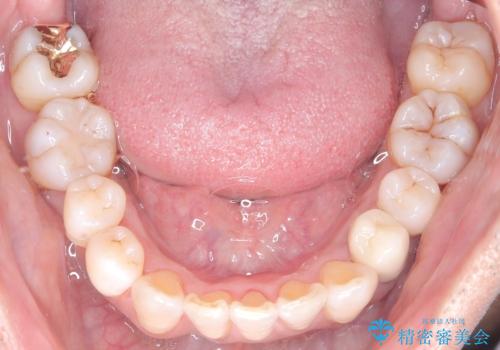

- 50代の患者様で、右上の八重歯と歯並びの乱れを気にされてご来院されました。特に、すでに装着されている前歯のセラミックブリッジを外したくないという強いご希望がありました。精密な検査の結果、八重歯を治すためのスペースが不足しているため、右上の4番目の歯(小臼歯)を抜歯し、そのスペースを利用して歯並び全体を整える治療計画を立案。装置には目立たないインビザラインを採用し、ブリッジを温存しながら八重歯の改善を目指しました。

今回の治療で最も重要だったのは、患者様のご要望通り既存のセラミックブリッジを外さずに矯正を進める点でした。計画通り右上の小臼歯を抜歯し、透明なインビザラインを使用して抜歯スペースを閉じながら、八重歯を正しい位置へ移動させました。ブリッジの形態と調和するに、他の歯の移動を工夫をすることで、複雑な条件をクリア。治療の結果、長年気にされていた八重歯が解消され、見た目が大きく改善しました。50代からでも、ご自身の要望を叶えながら、美しく機能的な歯並びを獲得していただけました。